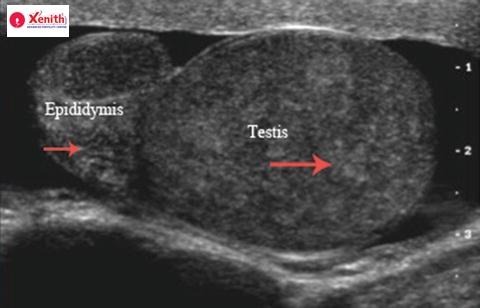

2. Scrotal Ultrasound

A scrotal ultrasound is painless and provides a clear image of the:

- Epididymis

- Testes

- Any cysts or swelling

- Evidence of obstruction or inflammation

It can detect cysts, structural abnormalities, and signs of epididymal congestion.